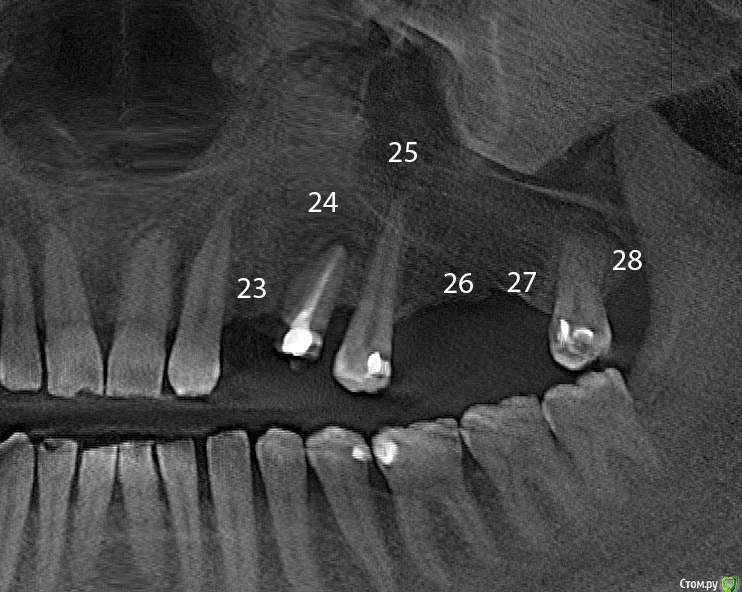

alex_ddd Опубликовано 28 июля, 2016 Автор Поделиться Опубликовано 28 июля, 2016 (изменено) Уважаемые господа! Спасибо за участие и отклики.Я только сейчас осознал, что запутался в номерах зубов и, вероятно, кропами фотографий сбил и вас с толку. Дело вот в чем: у меня на левой стороне верхней челюсти нестандартное расположение зубов - клык сразу идет вторым,3-ий , (где имплантант стоял до вчерашнего дня) это не выпавший молочный зуб.За ним идет 4-ый по счету, полагаю, вы говорите о нем. Его состояние плачевное? да?За ним 5-ка. Я ее депульпировал, потому что собирался ставить мост (жалею сейчас). Потом у меня нет нифига.. как видите, ну хоть синус лифтинг сделал на месте 6 И 7. Жду приживления.Я прикрепляю 2 фото, на нем я выставил номера. Если плох 24 зуб, что же мне следует предпринять? Заранее спасибо за ответы. да, с 2-й нет пока ясных ощущений, то ли чуть лучше, то ли так же.. Изменено 28 июля, 2016 пользователем alex_ddd Ссылка на комментарий

stommm Опубликовано 28 июля, 2016 Поделиться Опубликовано 28 июля, 2016 Можете попробовать сделать прицельный снимок зуба 24 (4-ка слева). Возможно там будет видно лучше. Если имеющийся снимок достоверен, то зуб скорее всего на удаление и имплантация 23, 24. Ссылка на комментарий